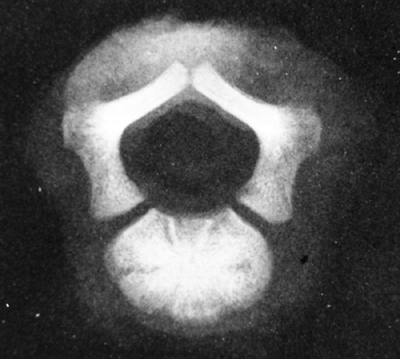

neural compression at the foramen magnum. This neural compression

occurs most likely because of asynchronous growth between the neural

elements and the skull base, which is formed by endochondral bone (12). The foramen magnum is small for age in all infants with achondroplasia, although there is some “biologic variability” (27,28). Diminished foramen magnum measurements have been correlated with respiratory dysfunction and delayed motor development (24) (Fig. 8.3), although other studies have not shown a correlation between hypotonia and foramen magnum size (29).

![]() |

|

Figure 8.3

Magnetic resonance image (MRI) of a child with achondroplasia shows stenosis at the foramen magnum. (Courtesy of George S. Bassett, MD) |